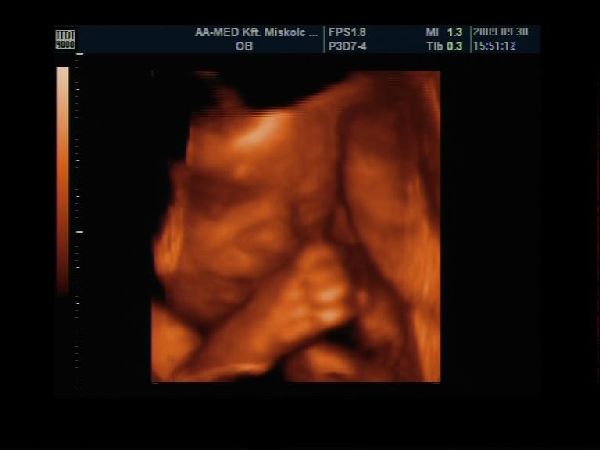

Van egy pár percem a gép előtt, gyorsan teszek fel Nektek képecskéket :wink:

Szerintem olyan szép pofija van és természetesen nekem Ő a legszebb :lol: :lol: :lol:

Szerencsére szépen mutatta magát, láttuk mindenét, most már biztos, hogy cunis :lol:

Apa is nagyon élvezte, főleg, hogy ennyire jól lehetett látni a kis tündérkénket :D

A képek 27 hetese és 1 napos: Kép Kép Kép Kép